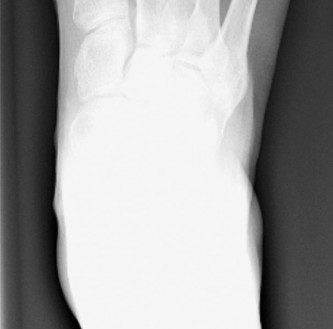

A 39-year-old female presents with increasing pain over the lateral aspect of her

foot. She complains of difficulty with shoe wear. She reports pain specifically at the lateral aspect of her fifth metatarsophalangeal joint. A weight-bearing AP radiograph was obtained (Fig. 5–81).

Figure 5–81 Weight-bearing AP radiograph of the foot.